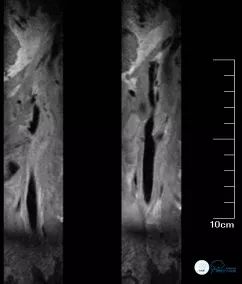

该患缘于入院前1月余无明显诱因出现发作性右侧肢体无力伴言语不清症状10余次,表现为言语笨拙,右上肢抬举无力、右手抓握能力下降,行走拖曳,向右侧倾斜,需人搀扶,每次持续约1-2分钟不等后,上述症状完全缓解。病程中患者无头晕、头痛,无恶心、呕吐,无视物模糊及视物旋转,无耳鸣及耳聋,无抽搐及意识不清。2018年5月6日就诊于北京某医院,完善头颅MRI:DWI示左侧基底节、放射冠、半卵圆中心、顶叶见点片状异常高信号(图1),诊断为“脑梗死”,住院静点药物(具体不详),治疗后患者未遗留症状;住院期间行头颈CTA提示:左侧颈内动脉闭塞(图2)故来诊。

头颅MRI(2018-05-10): DWI示左侧基底节、放射冠、半卵圆中心、顶叶见点片状异常高信号。(图1)